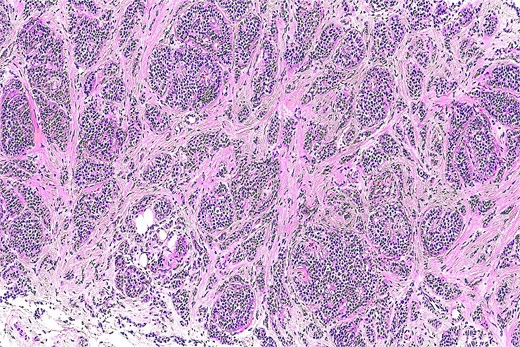

Histopathological analysis revealed a well-circumscribed dermal tumor composed of epithelial and myoepithelial cells arranged in nests and tubules embedded in a chondromyxoid stroma. The epithelial cells displayed bland cytology without atypia or mitotic figures. No infiltrative growth was observed.

Immunohistochemistry confirmed the diagnosis, with strong S-100 protein expression in myoepithelial cells and cytokeratin AE1/AE3 positivity in epithelial components (Fig. 3).

Histological section showing a well-circumscribed tumor composed of epithelial nests and tubules embedded in a myxoid and chondroid stroma (H&E, original magnification ×100).